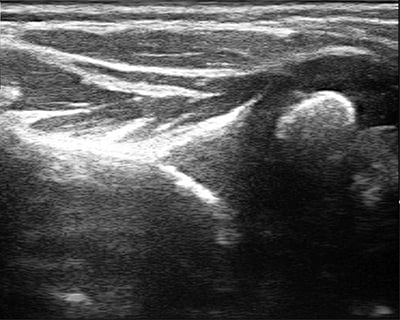

If the shoulder is left untreated, it can deform as it grows, a condition known as glenohumeral dysplasia (Figure 3a). Glenohumeral dysplasia can get worse with age but can be severe even in children as young as three months old. Some children may dislocate the shoulder joint completely.

Figure 3a: Severe glenohumeral dysplasia on ultrasound

Many patients come to us too late to implement the teapot splint, and shoulder tightness with internal rotation has already set in. In children less than a year of age, it may be possible to stretch out the shoulder using botulinum toxin to temporarily weaken the muscles that turn the shoulder in, and then to cast the shoulder in a position of external rotation (Figure 4). This has to be done with the child asleep and so requires general anesthesia. Ultrasound is used to confirm that the joint is in place after the shoulder is stretched, and is it also used intermittently after the cast is removed to make sure that the shoulder is growing and developing well. A teapot splint may be used after casting for up to two years during sleep to maintain the shoulder position.